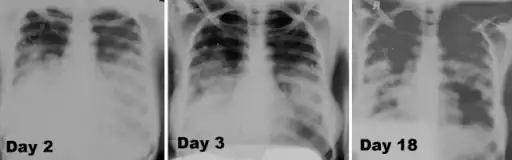

Image -primary pneumonic plague obtained on illness days 2, 3, and 18 shows bilateral lower lung zone predominant airspace disease associated with bilateral pleural effusions